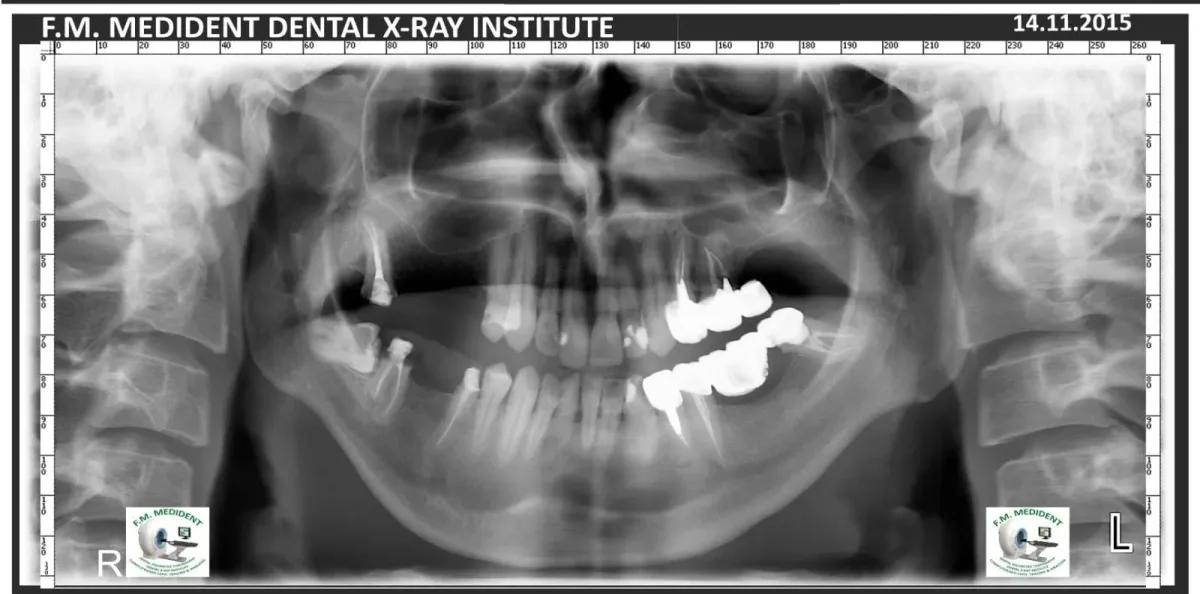

Cazuri reale înainte și după, din tratamente realizate în clinică.

Înainte

DupăExemple reale din cazuri tratate în clinică.